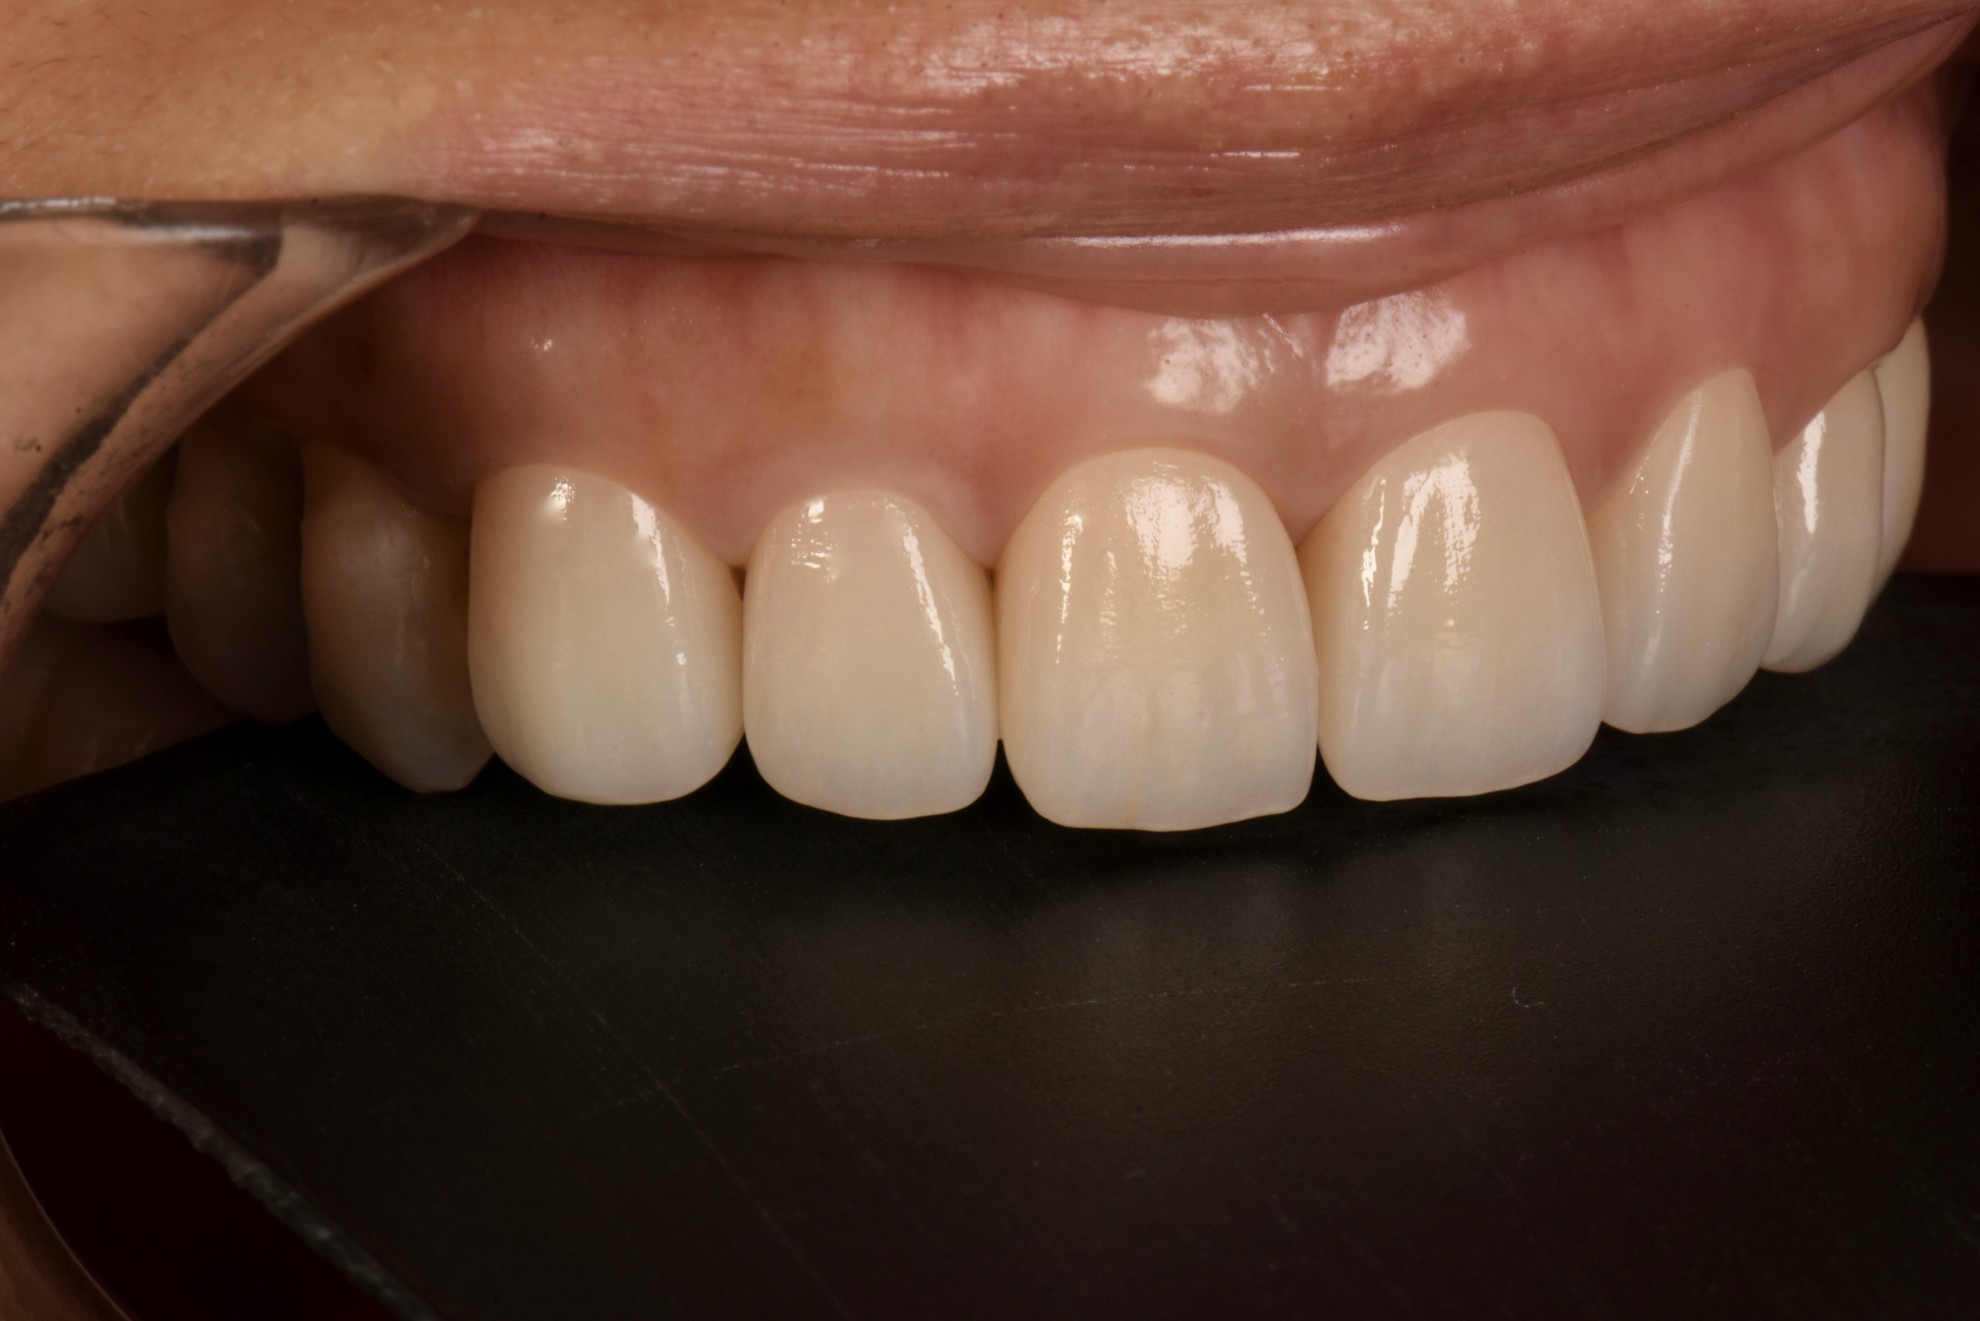

治療後

案例一